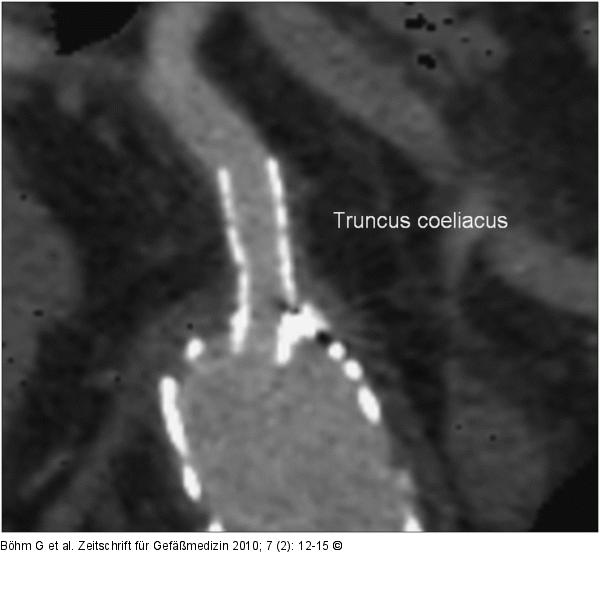

Abbildung 5: CT - MIP-Rekonstruktion CT MIP-Rekonstruktion: Stent im Abgang des Truncus coeliacus |

Abbildung 5: CT - MIP-Rekonstruktion

CT MIP-Rekonstruktion: Stent im Abgang des Truncus coeliacus |